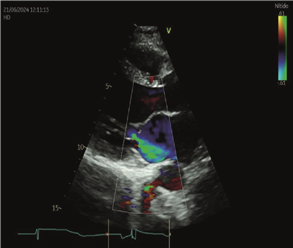

Los controles con ecocardiograma evidenciaban VI dilatado. Disquinesia septal e hipocontractilidad global.

FEVI 40-41%, AI moderadamente dilatada. Insuficiencia mitral leve. Insuficiencia tricuspídea leve con presión sistólica de la arteria pulmonar de 24 mmHg. Sin otros cambios con respecto al ecocardiograma previo al embarazo (figuras 1 y 2).

Figura 2. Ecocardiograma Doppler Transtorácico que muestra apicalización del cierre de la válvula mitral con tenting asimétrico que genera jet de regurgitación excéntrico de grado moderado.